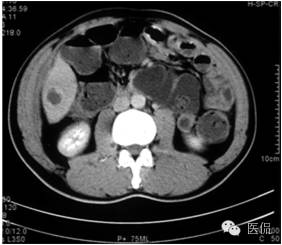

门脉期上述部位持续强化,程度加重,且环壁影增厚,核心样结节、分隔明显。